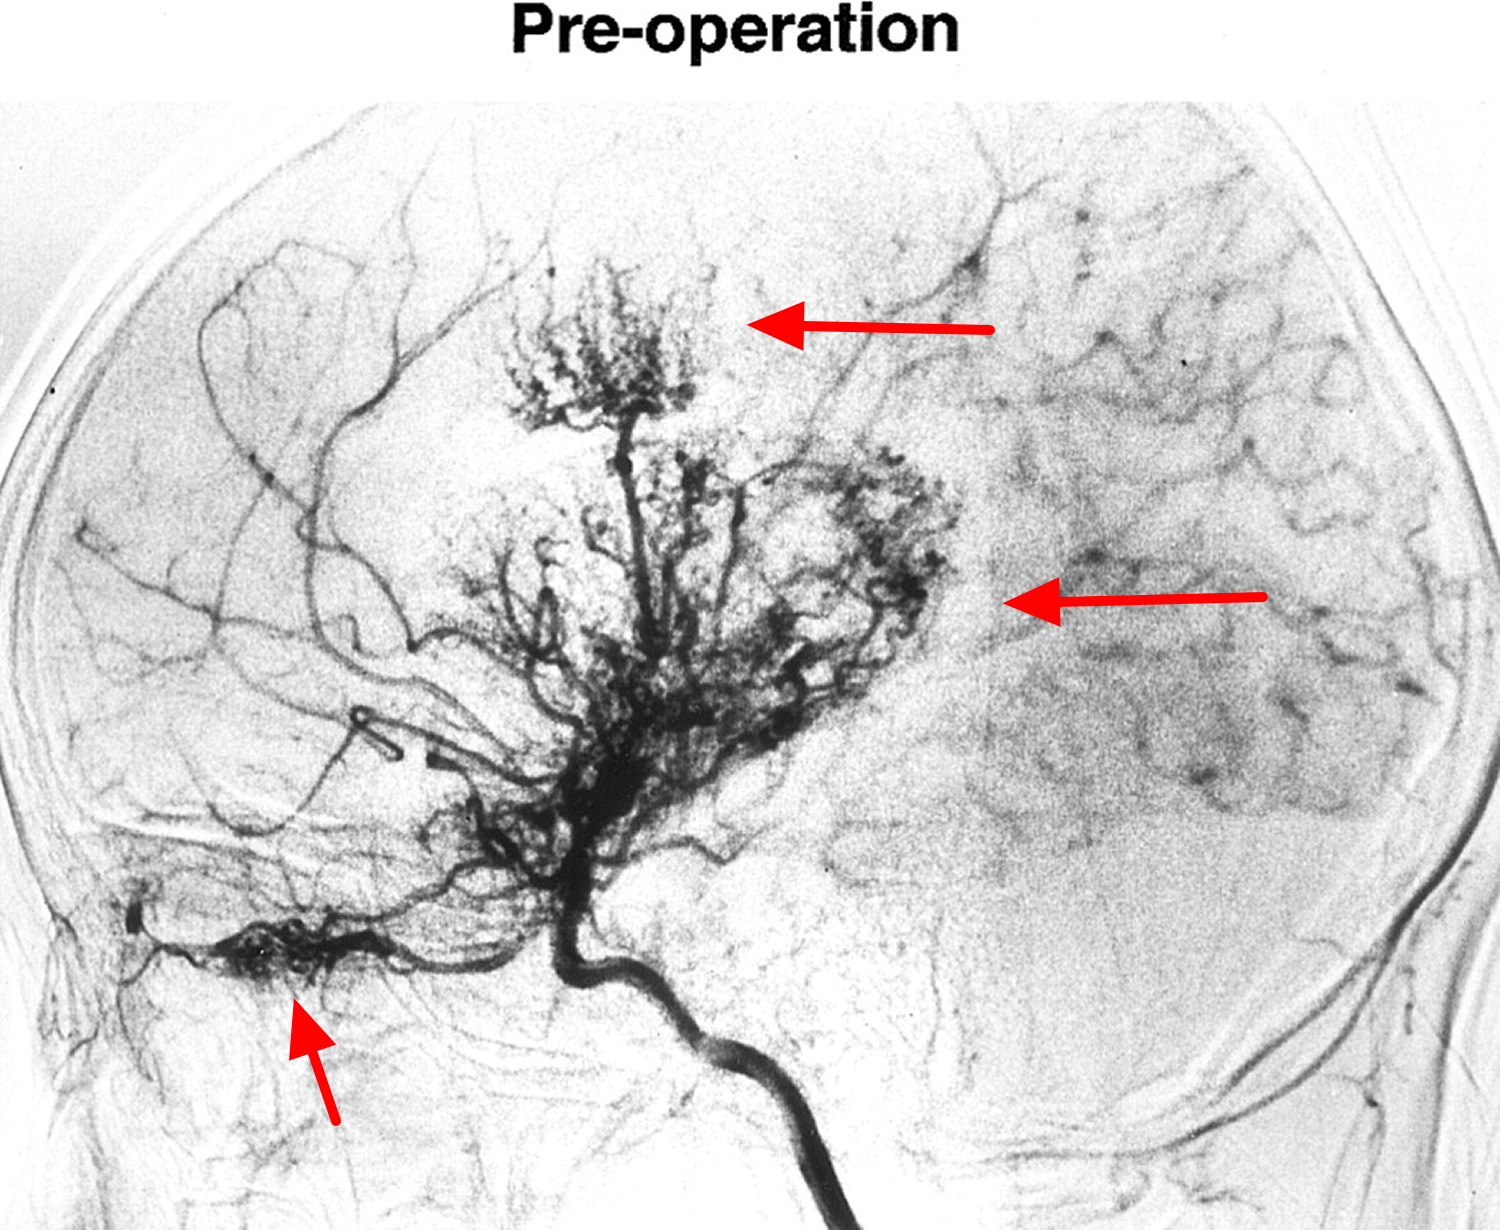

From the Japanese for “puff of smoke", this rare disease causes narrowing of the large intracranial arteries which gives rise to tiny collaterals vessels that have a tangled appearance on cerebral angiography:

What is Moyamoya disease ?